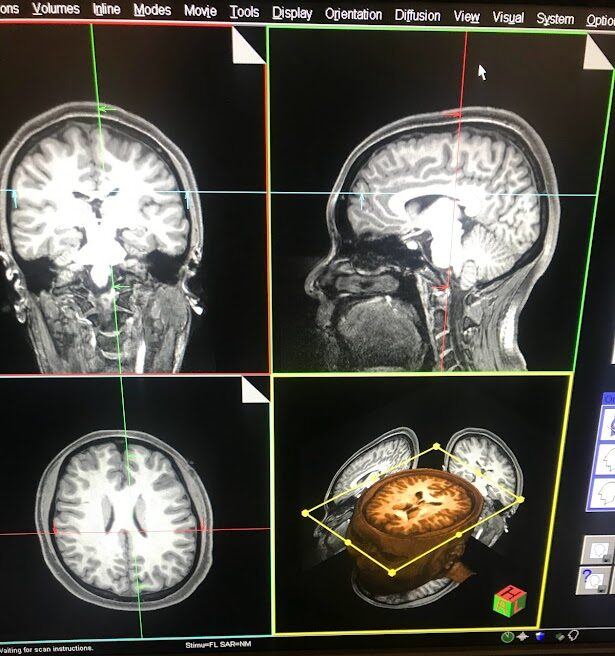

I Got My Brain Scanned for Science

Yeah, I got my brain scanned for science. And you should too! (If you’re eligible, that is.)

Basically, I got an MRI scan of my...